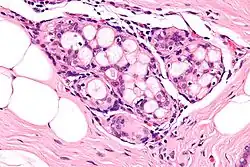

| Micrograph of collagenous spherulosis with the characteristic histomorphology - intratubular eosinophilic material with a spoke-like arrangement. H&E stain. | |

Collagenous spherulosis is characterized by a tubular/cribriform architecture with intratubular eosinophilic material that classically is arranged like the spokes of a wheel ("radial spikes"). There is usually no mitotic activity, and two cells populations (epithelial & myoepithelial) are present, like in benign breast glands.

The lesions are typically small (less than 50 spherules per lesion, less than 100 micrometers in size) and may be multifocal.